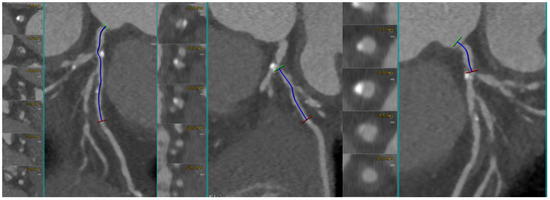

In summary, CCTA enables the comprehensive, quantitative assessment of bifurcation anatomy and plaque distribution, offering insights unattainable with conventional angiography. By combining anatomical, morphologic, and quantitative data, CCTA-derived risk models guide personalized bifurcation strategies, improve procedural planning, and may ultimately reduce periprocedural complications. Therefore, CCTA enables more accurate bifurcation analysis—including precise MV-SB angle assessment—and thus helps identify the most suitable two-stent strategy, including DK-crush, Culotte or TAP technique. As shown in Figure 4, CCTA provided a detailed anatomical assessment of a complex true LM–LAD–LCx bifurcation lesion (Medina 1.1.1). The dataset allowed for the accurate measurement of lesion length in both the main and side branches, supporting the precise identification of landing zones and appropriate stent sizing. Furthermore, CCTA enabled the exact definition of the distance between the LM ostium and the carina, guiding the optimal balloon length selection for POT.

Figure 4.

CCTA assessment of a complex true bifurcation lesion (Medina 1.1.1). Curved MPR and cross-sectional views allow for the accurate measurement of lesion length in both the main branch (MB) and side branch (SB), enabling precise landing zone definition and stent length selection. CCTA also provides an exact estimation of the distance between the left main (LM) ostium and the carina, which is essential for selecting the appropriate balloon length for the proximal optimization technique (POT). Abbreviations: LM, left main; LAD, left anterior descending; LCx, left circumflex; MB, main branch; SB, side branch; POT, proximal optimization technique.

As shown in Figure 5, the final angiographic result demonstrates the successful treatment of the bifurcation lesion using a two-stent strategy (TAP technique), with optimal stent expansion, complete restoration of luminal patency, and final TIMI 3 flow in both the LAD and LCx.

Figure 5.

Final angiographic result. Angiography shows optimal lumen restoration following T-and-protrusion (TAP) stenting of the left main (LM) bifurcation involving the left anterior descending (LAD) and left circumflex (LCx). Abbreviations: PCI, percutaneous coronary intervention; LM, left main; LAD, left anterior descending; LCx, left circumflex; TAP, T-and-protrusion.